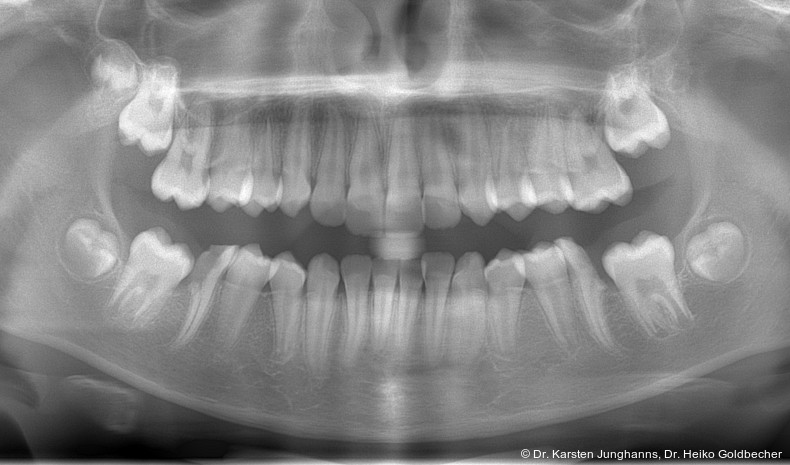

Eine Patientin stellte sich im Alter von neun Jahren erstmals vor. An den ersten Molaren des Unterkiefers wurden vom Hauzahnarzt eine MIH diagnostiziert (Abb. 1a) und die Zähne als nicht erhaltungsfähig eingestuft. Die beiden ersten Molaren wurden hemiseziert und der distale Anteil extrahiert. Gut zu erkennen ist auf dem OPG die annähernd achsengerechte Mesialisierung der zweiten Molaren sowie die Aufwanderung der Zahnkeime der dritten Molaren (Abb 1b: ca. 1,5 Jahre nach Hemisektion). Noch vor Durchbruch der zweiten Molaren in die Mundhöhle wurde auch der mesiale Anteil entfernt. Der spontane Lückenschluss erfolgte innerhalb der nächsten anderthalb Jahre (Abb. 1c). Die endgültige Achsstellung kann nach Ausdehnung der Teilmultibandapparatur eingestellt werden.